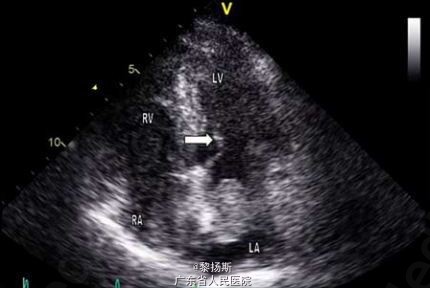

体格检查发现患者双侧膝盖网状青斑(图 1)。收入院时,患者体温 38.5℃,心率 165 次 / 分,呼吸 28 次 / 分,血压 89/50mmHg,血氧饱和度 94%(无额外吸氧)。心脏查体闻及 2/6 级全收缩期杂音,以心尖部最为明显,余检查未见明显异常。实验室检查发现白细胞增加至 15.7×109/L(参考值范围 3.8–11×109/L),中性粒细胞占 95%,血红蛋白 127g/L,血小板 306×109/L,C 反应蛋白升高至 73mg/L(参考值范围 0-5mg/L),另外,尿素和肌酐轻度增加,自身免疫抗体阴性,尿常规正常。心电图提示窦性心动过速,无 PR 间期延长,胸部 X 线检查无异常。血培养结果提示存在少酸链球菌(S. acidominimus),对青霉素和红霉素灵敏。进一步经食道超声心动图(TTE)检查提示左房纵向扩张,伴一大小为 2.8×3.2cm,附着于房间隔的部分活动性结构(图 2)。另外,二尖瓣上也附着有赘生物(图 3)。